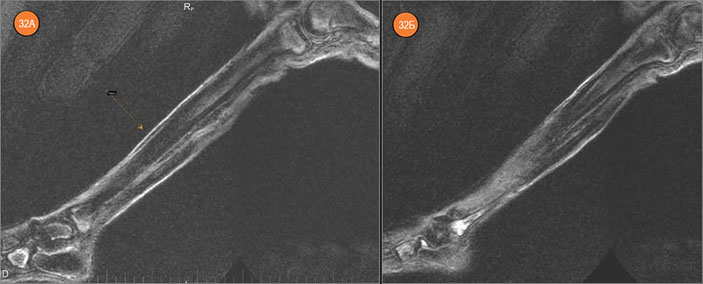

В латеральной лодыжке (левая малоберцовая кость) имеется зона резкой отечности губчатого вещества до 15×25×10 мм; аналогичный очаг до 12×15×10 мм — в дистальном эпифизе левой большеберцовой кости. Правая большеберцовая и малоберцовая кости находятся в хорошем состоянии, без явных очагов, имеются лишь мелкие субхондральные отечно-склеротические изменения.

Рис. 32. Левая голень. А — большеберцовая кость. Б — малоберцовая кость

В костях левой стопы выявлены очаги с отечной периферией и с МР-плотными темными центральными зонами. Эти изменения можно интерпретировать как проявления прижизненного инфекционного или, что более вероятно, метастатического процесса. Аналогичные, но менее интенсивные очаги выявлены в костях правой стопы.

Рис. 33. Правая голень — большеберцовая кость. Рис. 34. Правая голень — малоберцовая кость, дистально (А) и проксимально (Б)